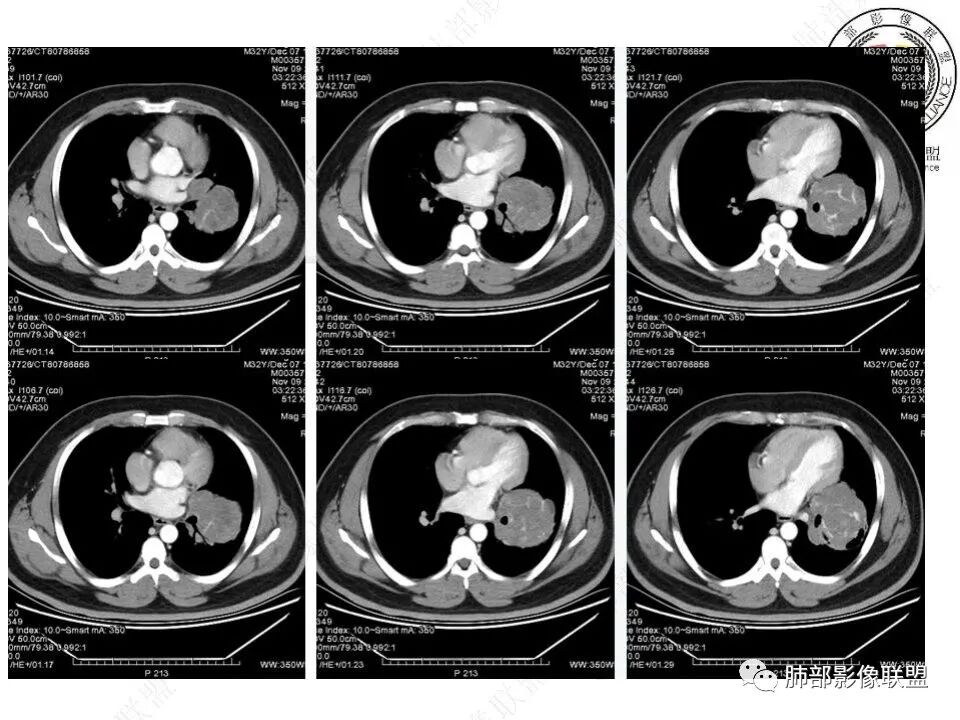

青年男性,体检发现左肺不规则类圆形占位性病变,叶间裂区域,定位胸膜来源。左肺下叶支气管受压狭窄,但管壁光整,未见腔内阻塞或管壁受侵。包块边界清晰,浅分叶,内部密度不均匀,病灶后份见空气新月征。渐进性强化,增强动脉期见分支状血管,蛇纹血管征。肺门纵膈未见增大淋巴结,符合孤立性纤维瘤(SFT)。

3)肺部SFT好发于肺表面如叶间裂等区域,定位相当重要。肿块边界清楚光整,支气管不受侵(或可受压推移)。CT平扫肿瘤多呈等或稍低密度。发生于脑膜的SFT平扫肿瘤多为略高密度病,类似脑膜瘤;肿瘤较小者密度均匀,较大者内部密度常不均匀、见多发灶性或不规则形中心低密度区(细胞稀疏区含有丰富胶原纤维易发生黏液样变性或囊性变),钙化少见。

5)肿瘤的强化程度及方式:增强扫描肿瘤早期实性成分呈不均匀斑片或斑驳样强化,亦可呈“ 地图样” 明显强化,强化程度不一,可呈轻度-显著强化;静脉期持续强化,多期增强及动态增强扫描均呈“快进慢出”型强化,且强化范围逐渐增大并趋均匀。肿瘤内部及周围常见多发粗细不等强化或流空肿瘤血管影。瘤体内“蛇纹血管”在其他诸如硬化性肺细胞瘤、错构瘤等等是非常罕见的。